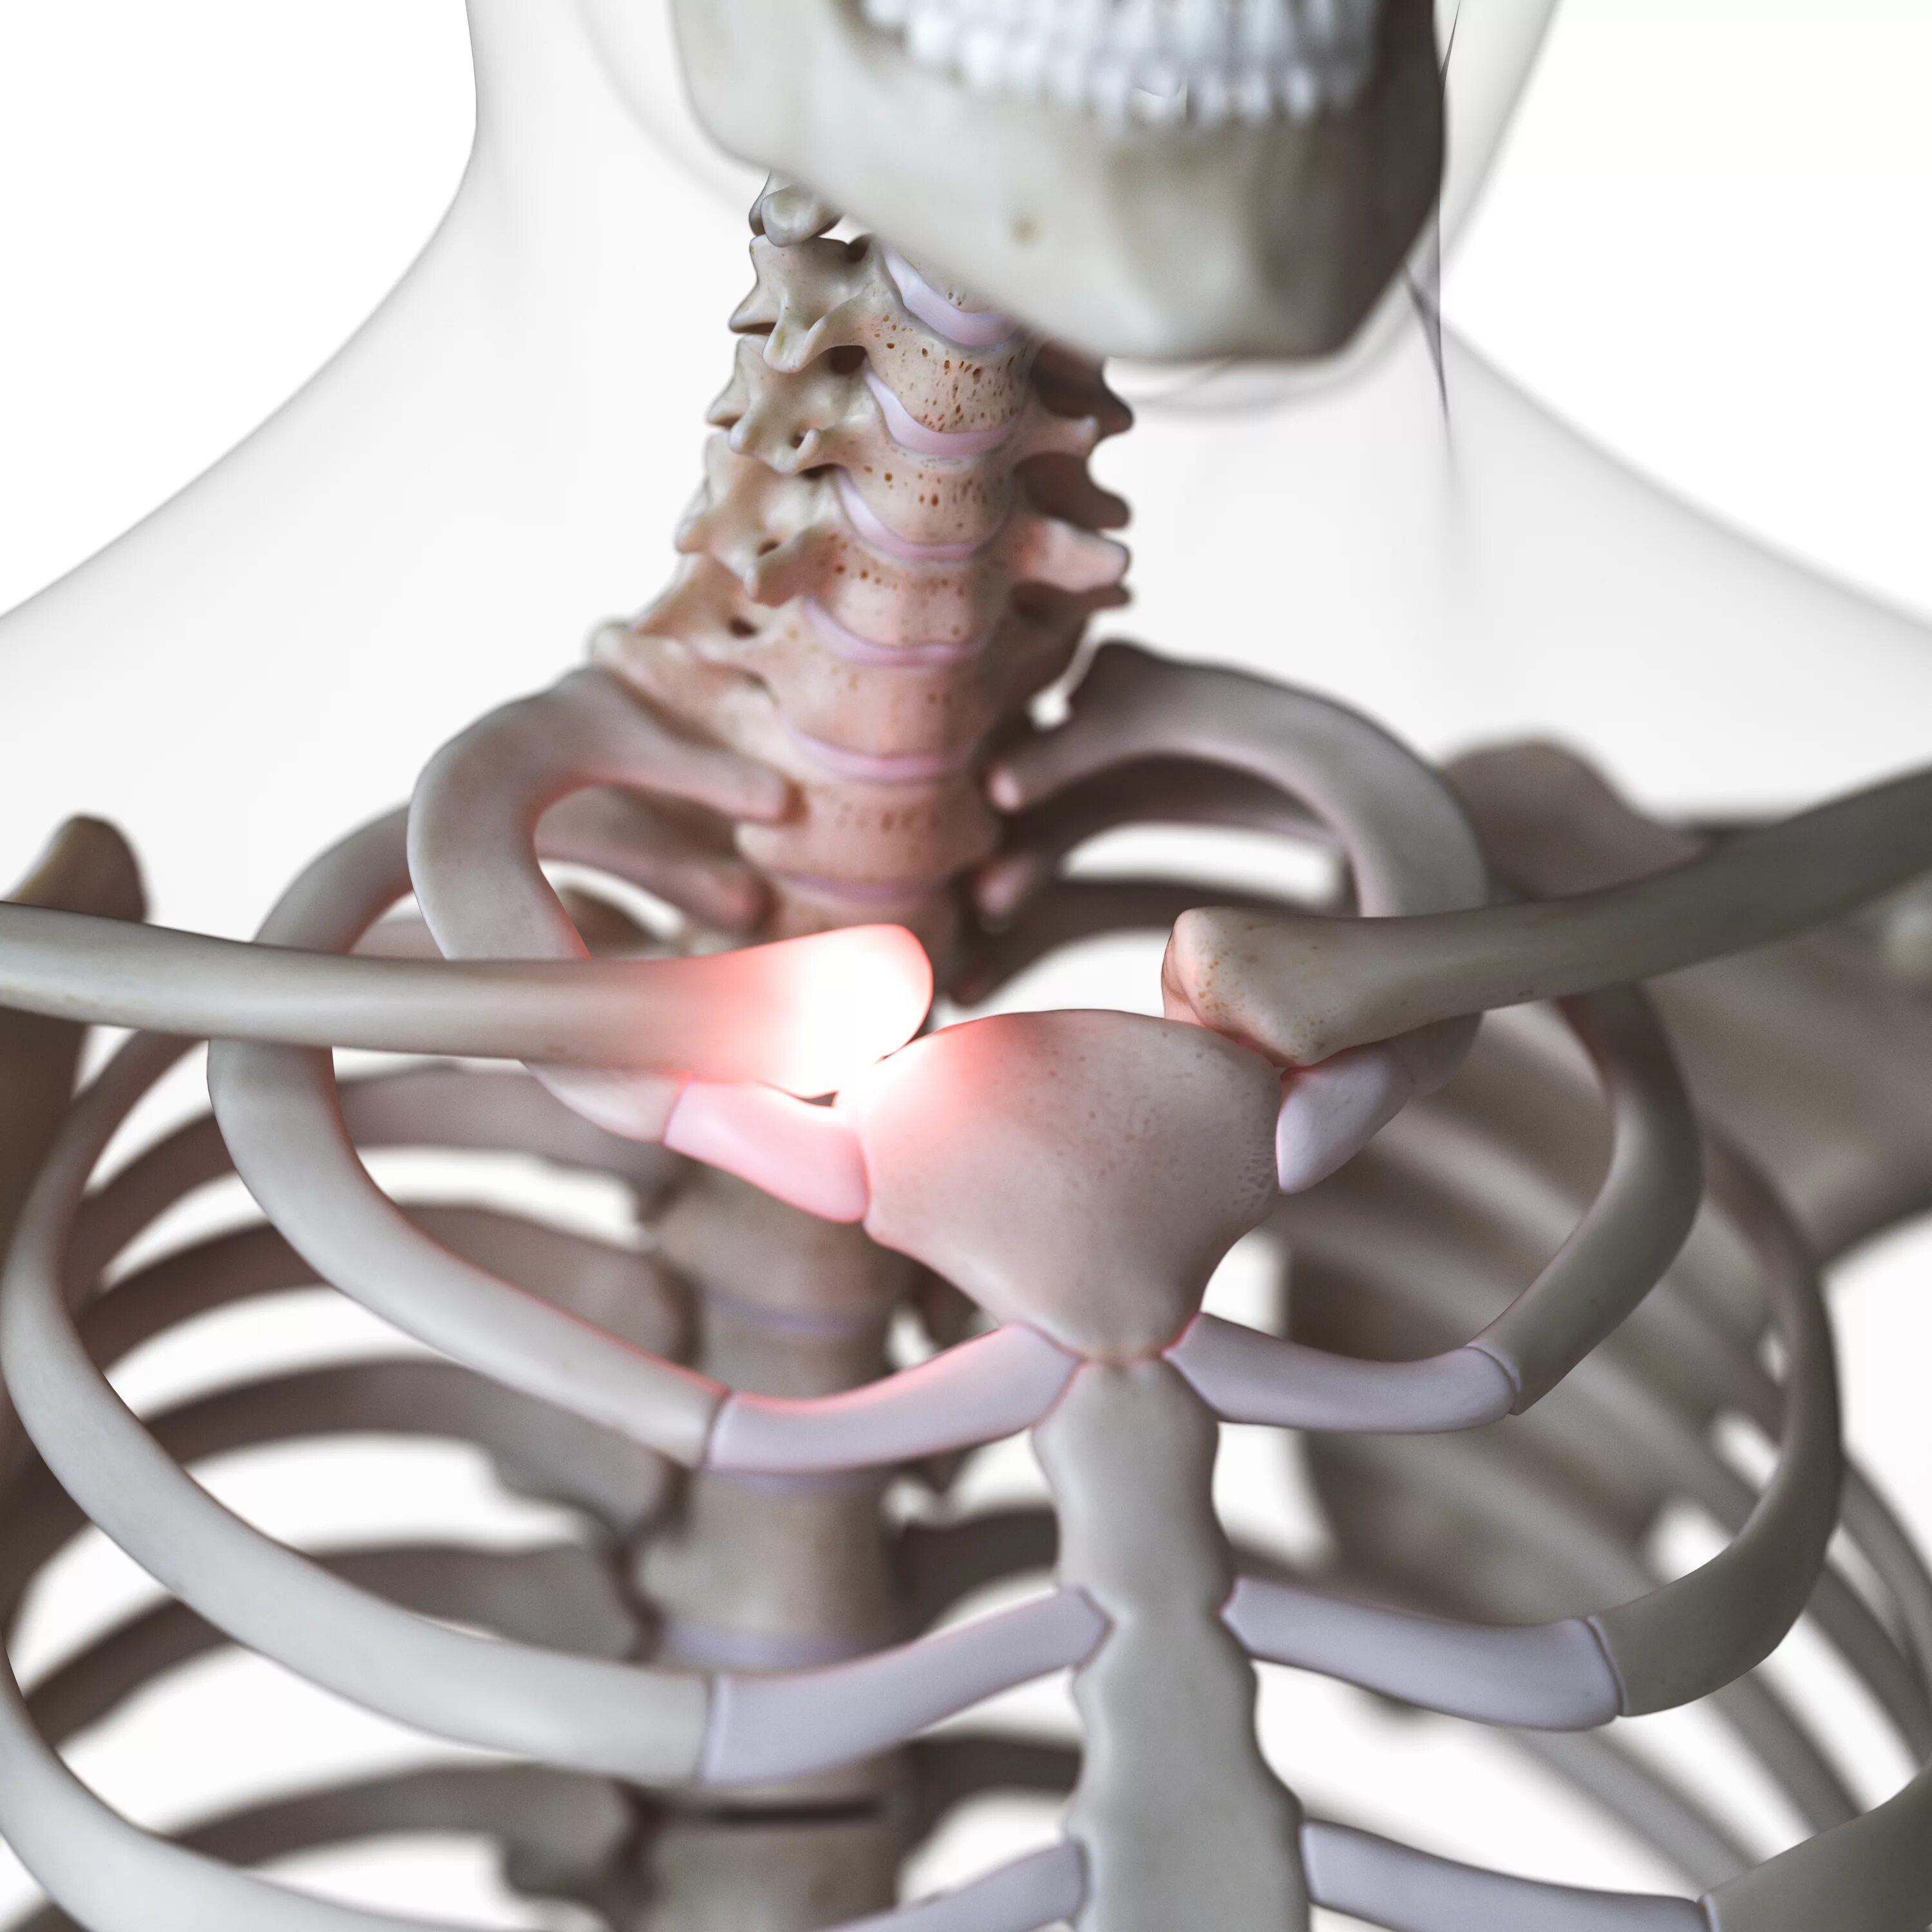

Грудино ключичная артрит